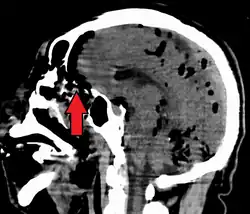

Pneumocephalus is the presence of air or gas within the cranial cavity. It is usually associated with disruption of the skull: after head and facial trauma, tumors of the skull base, after neurosurgery or otorhinolaryngology, and rarely, spontaneously. Pneumocephalus can occur in scuba diving, but is very rare in this context.

CT scans of patients with a tension pneumocephalus typically show air that compresses the frontal lobes of the brain, which results in a tented appearance of the brain in the skull known as the Mount Fuji sign.[1][2][3] The name is derived from the resemblance of the brain to Mount Fuji in Japan, a volcano known for its symmetrical cone. In typical cases, there is a symmetrical depression near the midline (such as the crater of a volcano), due to intact bridging veins.[3] Its occurrence seems to be limited to tension pneumocephalus (not occurring in pneumocephalus without tension).[4] The sign was first described by a team of Japanese neurosurgeons.[5]